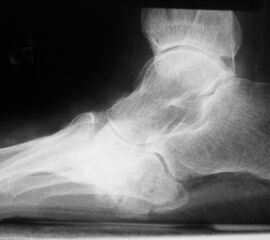

Der Knickfuß geht in der Regel mit einer abgeflachten Längswölbung (Senkfuß) und im fortgeschrittenen Stadium mit einer Aufhebung der Längswölbung (Plattfuß = Pes planus) (Abb. 2a) einher. Man spricht dann von einem sogenannten Knick-Plattfuß (Pes plano-valgus) 8. Beim DFS gilt es einen vorbestehenden Plattfuß, der evtl. noch flexibel ist, von einem strukturellen, kontrakten Plattfuß bei Einbruch des Fußlängsgewölbes im Rahmen einer Osteoarthropathie zu unterscheiden. Mit dem Jack‘s-Test lässt sich prüfen, ob der sog. Windlass-Mechanismus (Windenmechanismus) intakt ist (Mann 2013).

Ein Spitzfuß (Pes equinus) kann sowohl durch eine Verkürzung von Achillessehne, M. gastrocnemius und M. soleus, aber auch durch ein mechanisches Extensionshindernis im oberen Sprunggelenk bedingt sein. Folge der Spitzfußstellung ist eine deutliche Druckumverteilung mit Mehrbelastung des Vorfußes. Typisches Merkmal des Hohlfußes (Pes cavus) (Abb. 2b), welcher oft mit einer Rückfußvarusstellung kombiniert ist, ist ein pathologisch überhöhtes Fußlängsgewölbe. Er ist meist Folge neuro-muskulärer Grunderkrankungen.

Der Schaukelfuß oder Tintenlöscherfuß (Abb. 2c und d) ist beim Patienten mit DFS meist alleinige Folge einer Osteoarthropathie mit komplettem Einbruch des Fußlängsgewölbes durch eine Gelenkdestruktion im Bereich zwischen Lisfranc- und Chopartgelenk.

Eine Varus- oder Valgusdeviation des Vorfußes wird als Pes adductus (Sichelfuß) oder Pes abductus bezeichnet. Der häufigere Pes abductus ist bei fortgeschrittenem Plattfuß auf eine mediale Subluxation des Taluskopfes im Talonaviculargelenk zurückzuführen. Häufig findet sich eine Vorfußverbreiterung (Spreizfuß, Pes metatarsus) (Abb. 2e) mit sekundären Deformitäten der Zehen (Hallux valgus) und Zeichen eines chronischen Tiefertretens des Metatarsale 2-4 (Metatarsalgie, Fehlbeschwielung).